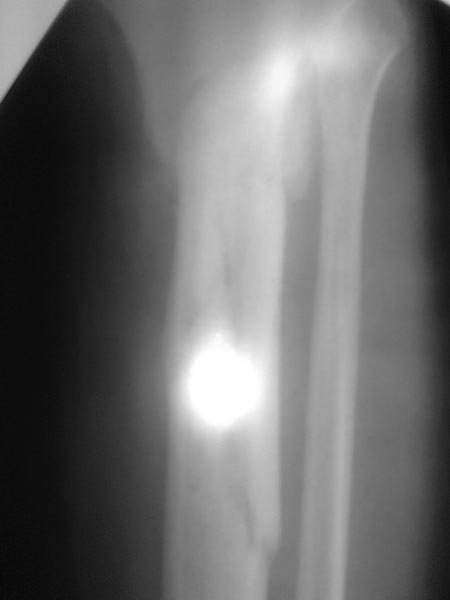

Re: Ложный сустав б/ берцовой с инфицированием

Спасибо за обсуждение.Отправил остальные R, изиняюсь за качество.

3.Перелом на 2 уровнях, есть искривление костно-мозгового канала. Проксимальный отломок короткий.